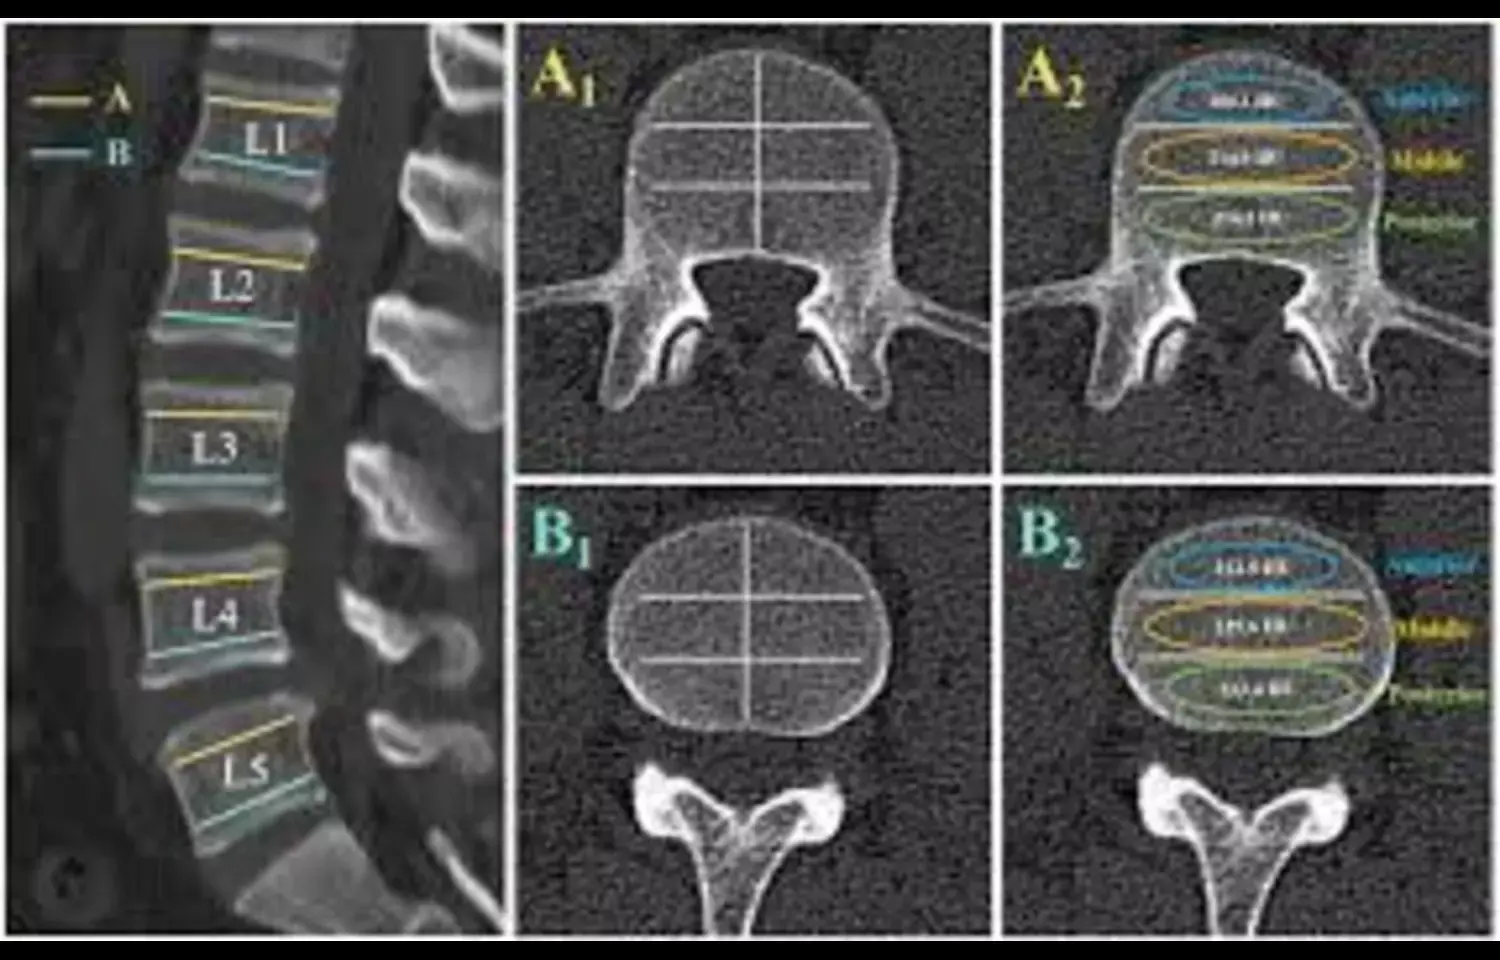

The relationship between insulin resistance (IR) and bone density is quite complex. The triglyceride glucose (TyG) index, which combines the assessment of glycolipid metabolism, can serve as a noninvasive alternative method for evaluating IR and is easy to promote. Currently, there is relatively little research on the correlation between the TyG index and bone density in postmenopausal women. This study explored the relationship between the TyG index and lumbar spine bone mineral density (LBMD) in elderly postmenopausal women in the United States through the National Health, and Nutrition Examination Survey (NHANES) database data. Using the NHANES database data from 2005 to 2018, the population was divided into 4 groups based on TyG data (<5.447, 5.447–5.879, 5.879–6.325, >6.325), and the differences among the groups were analyzed. Multiple linear regression analysis was used to examine the relationship between the TyG index and LBMD, and the beta (β) values and corresponding confidence intervals were calculated. Three models were constructed by adjusting for different variables. Additionally, curve fitting analysis was used to explore the nonlinear relationship between the 2 variables. Subgroup analysis was conducted to study the relationship between the 2 variables in different populations. The study included a total of 1880 postmenopausal women participants aged 50 years or older. The highest quartile of the TyG index had a greater proportion of Mexican Americans, lower levels of education, lower family income-poverty ratios, higher body mass indices, higher total cholesterol levels, and lower levels of 25-hydroxy vitamin D. The relationships between the TyG index and LBMD were significant in 3 models and were positively correlated. In sensitivity analysis, the Q4 group has an LBMD 0.0235 g/cm2 higher than the Q1 group. According to the subgroup analysis, this positive correlation continued to exist in the non-Hispanic Black population and also in the population with a high school education or below. The TyG index is positively correlated with LBMD in the population of elderly postmenopausal women, as shown by multiple linear regression, and a positive correlation also exists between the 2 as indicated by smoothing curve fitting. Further causal analysis requires investigation through cohort studies is needed.